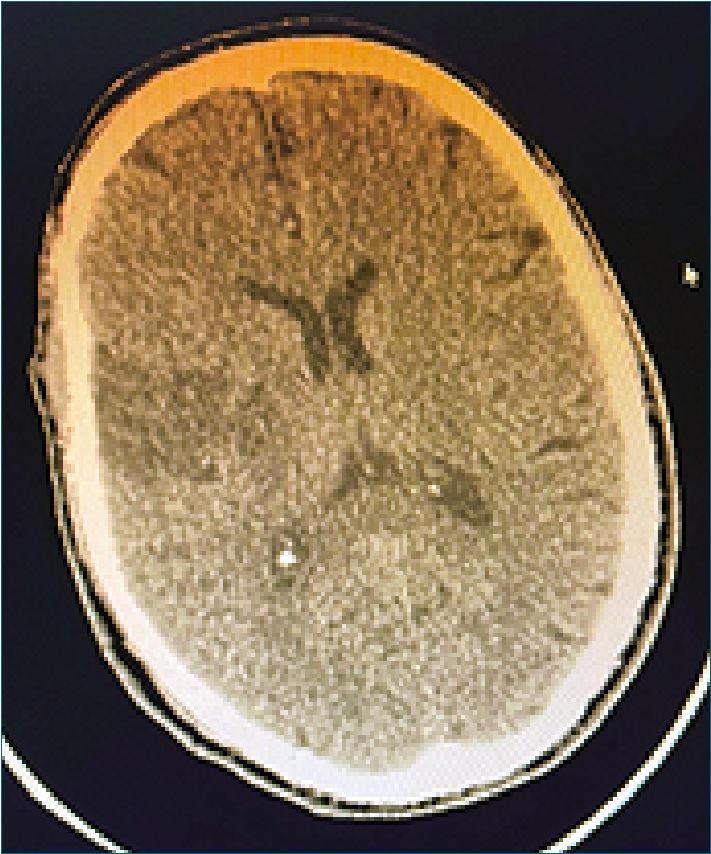

Control tomográfico a las 24 h evidencia hipodensidad subcortical y periventricular derecha que afecta la convexidad de la circunvolución parietal ipsilateral, lo cual sugiere una isquemia configurada (Figura 2). En la evolución paciente sin cambios clínicos, persistiendo con síndrome piramidal izquierdo proporcionado, con parálisis facial central y corticobulbar en etapa flexoespástica y Babinski a izquierda. El planteo diagnóstico fue infarto cerebral derecho de naturaleza tromboembólica. A los 15 días es dado de alta a domicilio.

Figura 2. TAC control a las 24 h, muestra configuración del área de isquemia subcortical parietal derecha.